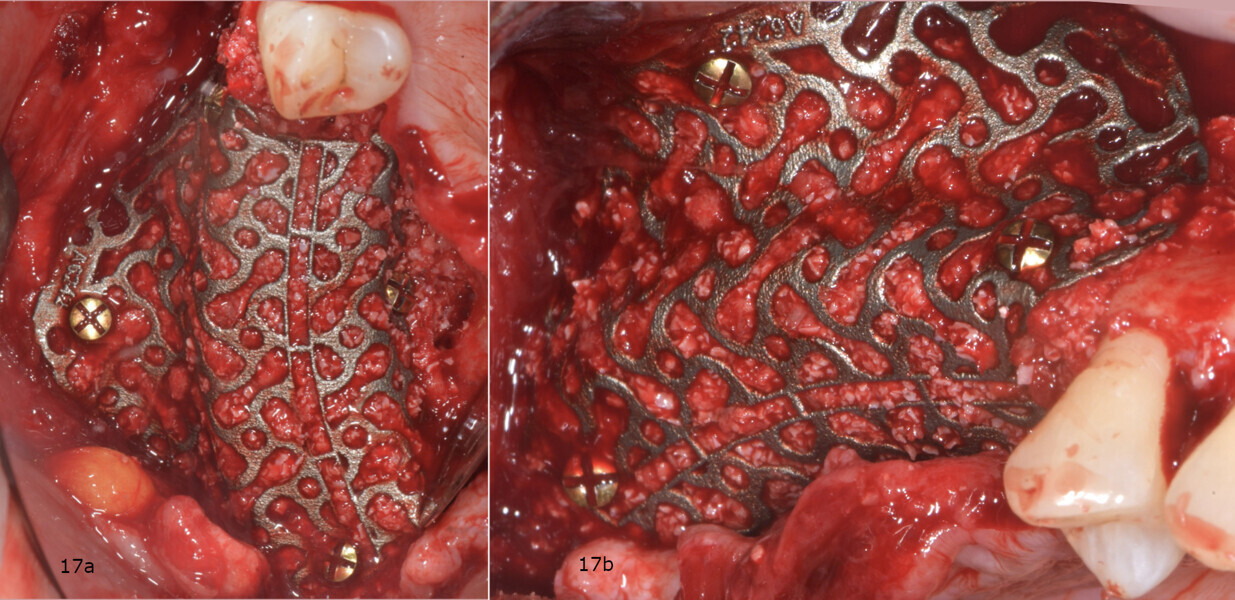

Subsequently, the customised CAD/CAM titanium mesh (Yxoss CBR, ReOss) was taken from the double sterile pouch and filled with the grafting material (Figs. 16a & b). The mesh was then positioned in place and fixed with four osteosynthesis screws (BT screw, BTK) to achieve absolute stability (Figs. 17a & b). It was then covered with a native collagen resorbable membrane (Geistlich Bio-Gide), which was stabilised with titanium tacks (MCbio, Geistlich; Fig. 18).